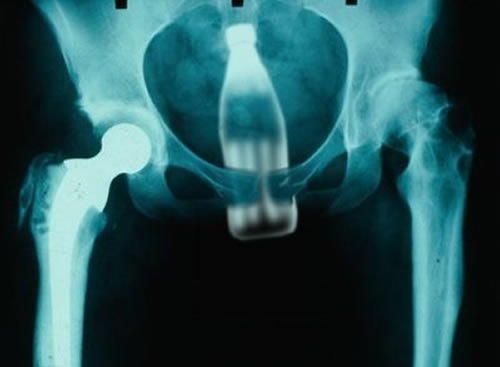

@trek post mortem xraypic.twitter.com/wZRIBgvHkB